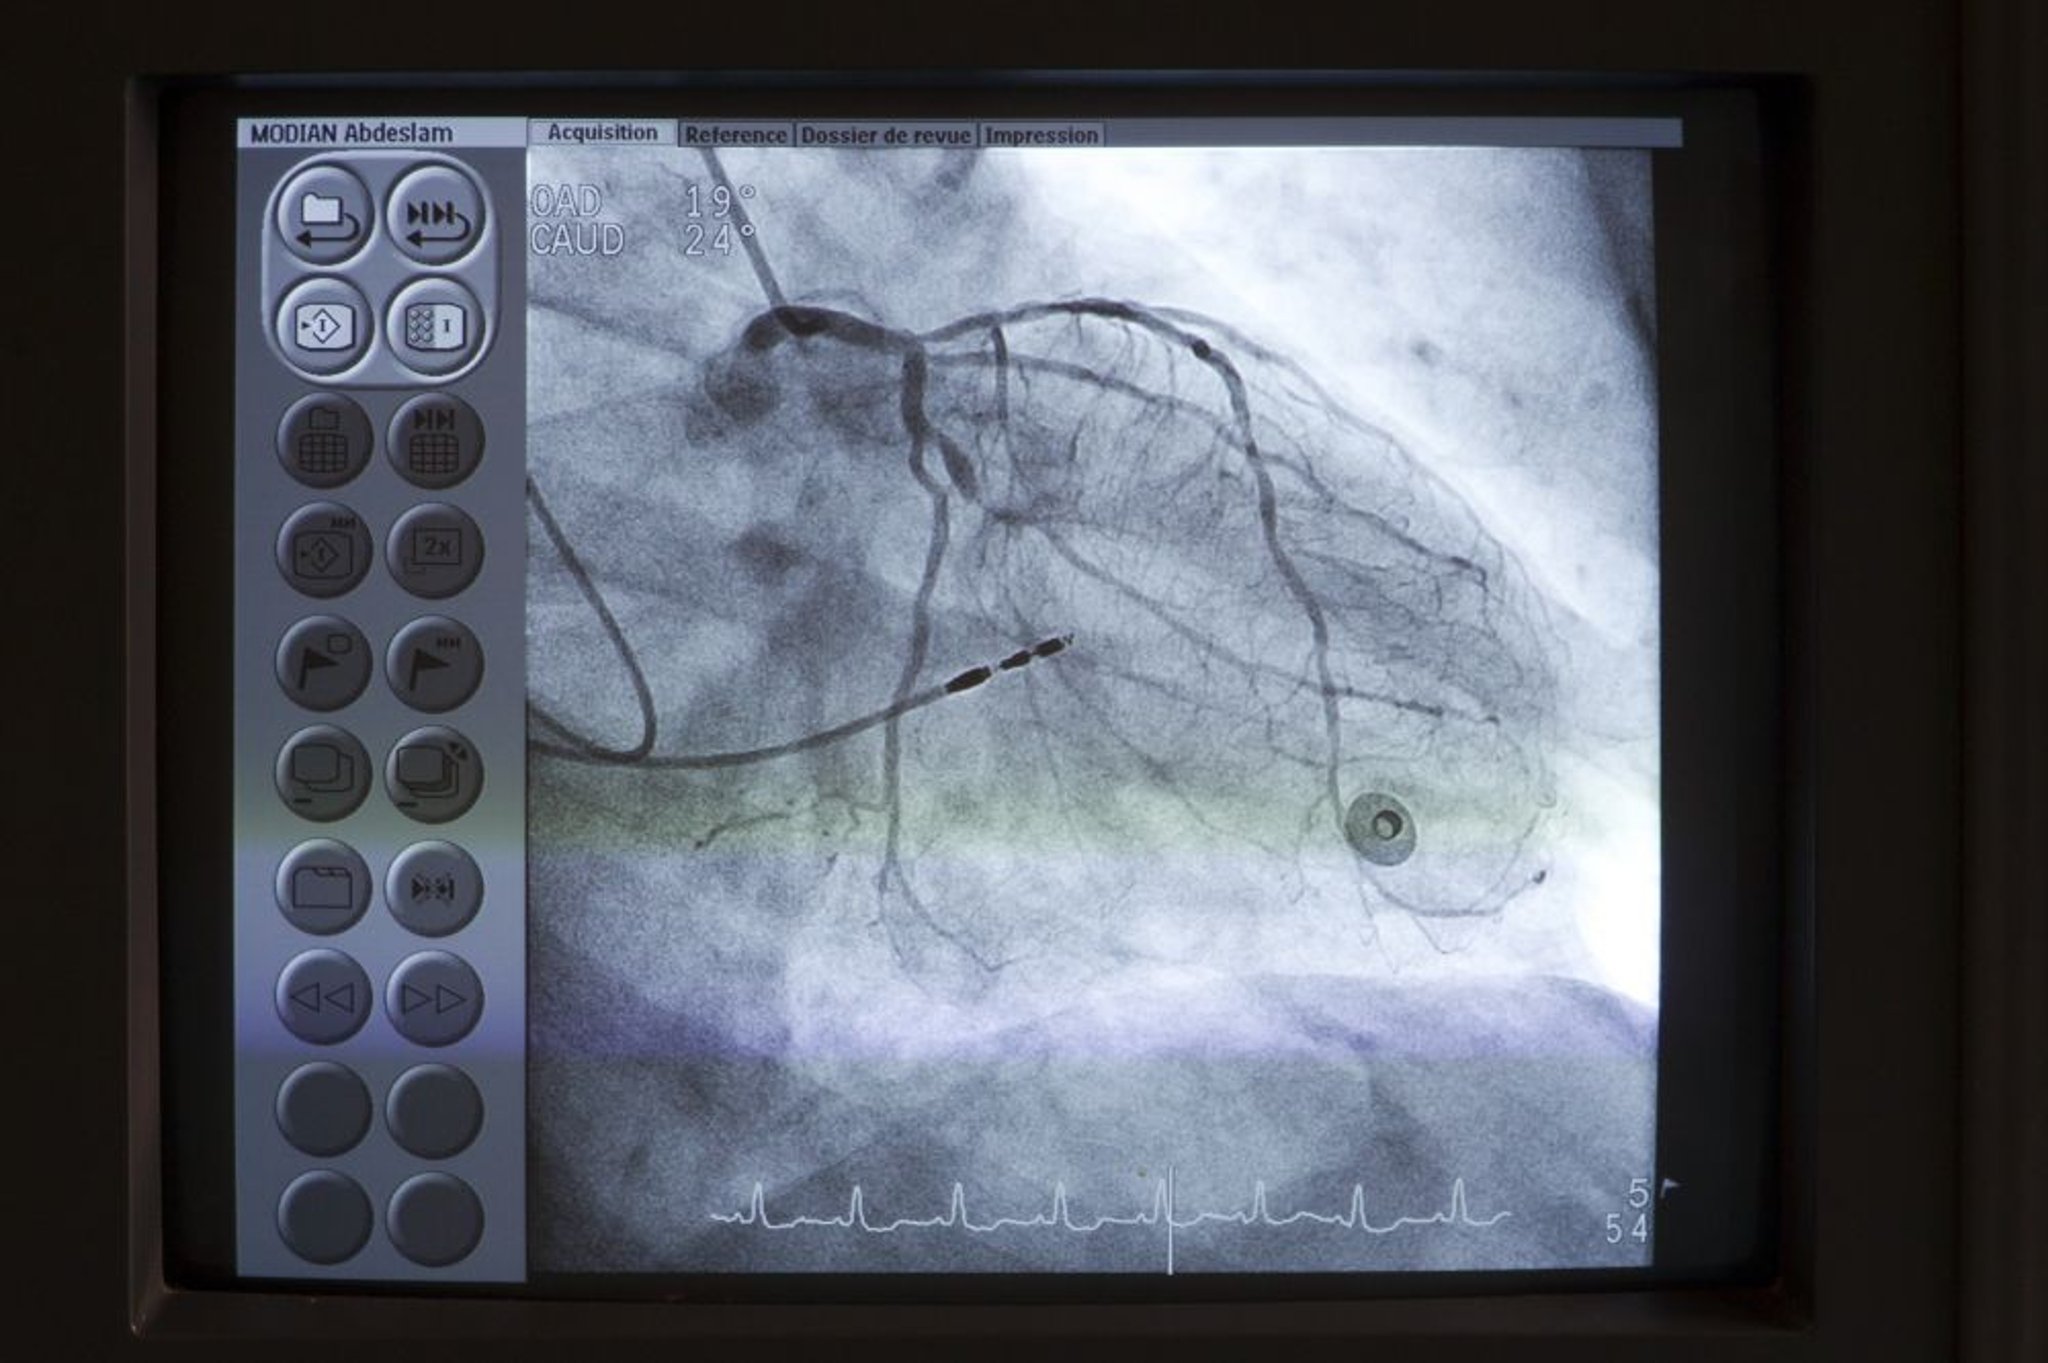

Angiografia coronariana

Um catéter (parte superior esquerda) é inserido no óstio da artéria coronária principal esquerda. O contraste é então injetado nas artérias coronárias sob fluoroscopia para detectar quaisquer anomalias, como estenoses.

Astier/BSIP/SCIENCE PHOTO LIBRARY